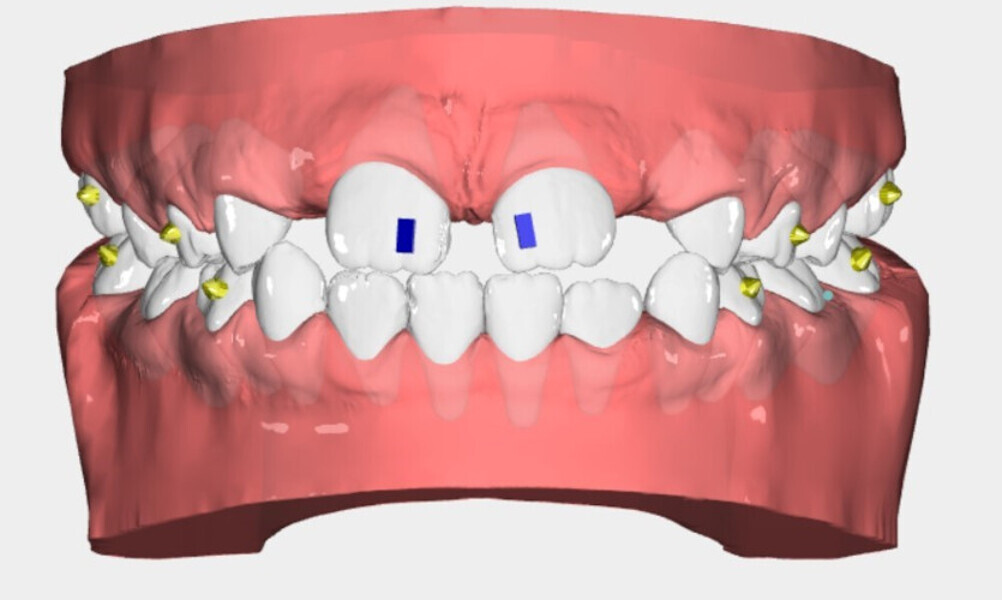

We decided to treat the patient with Nuvola Junior. Movement was to be achieved with 20 pairs of aligners initially, leaving eruption guides for teeth #12 and 22. The maxillary aligners used in the treatment have lingual pins (patented for the Nuvola OP system protocol) (Fig. 5) that prompt raising of the tongue tip towards the incisive papilla (Fig. 6). After the planned 20 pairs of aligners, eight finishing pairs were made especially to align teeth #12 and 22. The aligners were worn all night and for 2 hours during the day and changed every 14 days.

After 18 months of therapy, a case reassessment was carried out to verify that the goals had all been achieved (Fig. 8). Comparison of extra-oral photographs at the start of treatment (T0) and end of treatment (T1; Fig. 9) showed that excellent balance of the patient’s face had been achieved with a regular, symmetrical smile. Comparison of the intra-oral photographs (Fig. 10) and models (Fig. 11) also showed wider and more harmonious arch forms, closure of the anterior diastema, closure of the open bite and recentring of the mandibular midline. Excellent gingival trophism had also appeared.